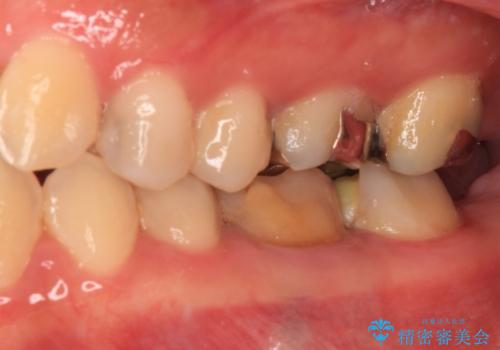

- 処置が必要と言われていたものの、長い間放置していた奥歯の治療を希望して来院された患者様です。

一番奥の歯は詰め物が脱離しており、仮詰め材が詰まっており、手前の歯は根管治療後に樹脂で固めたままの状態でした。

手前の歯を仮歯に置き換えるとともに、一番奥の歯のむし歯治療を行うこととしました。